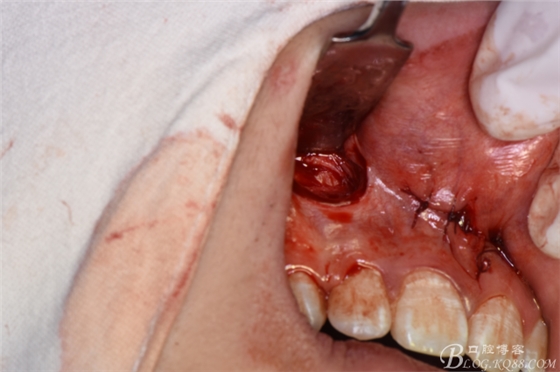

圖8.先拔除11、21之間多生牙,做唇側(cè)弧形切口

圖9.翻瓣、暴露唇側(cè)骨面,高速渦輪機去骨。